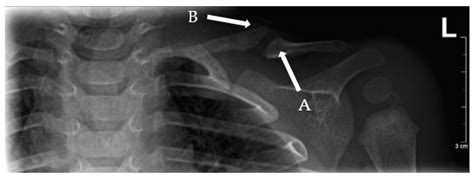

Diagnosing a broken collarbone in a newborn involves a physical examination and imaging tests. The healthcare provider will:

• Examine the baby's collarbone area for swelling, tenderness, and deformity

• Order an X-ray to confirm the fracture and assess its severity

In some cases, additional imaging tests such as an ultrasound or CT scan may be recommended to get a more detailed view of the injury.